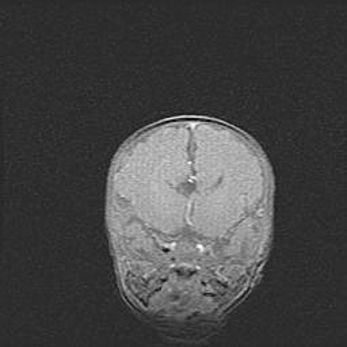

Множественные кисты обоих полушарий головного мозга, наибольшая из них в правой затылочной области. Ассиметричная атрофическая гидроцефалия.

Возраст: 7 месяцев

Вес: 5660 г

Пол: мужской

Окружность головы: 41,5 см

Срок гестации: 28-29 недель

Кисты головного мозга развиваются в результате многоочаговых некрозов вещества мозга и возникают вследствие перенесенной перинатальной инфекции, менингитов, энцефалитов, асфиксии, родовой травмы, расстройств мозгового кровообращения различного генеза. Образованию кист в веществе головного мозга плодов и новорожденных способствуют такие факторы, как высокое содержание в нем воды, недостаточная (или отсутствие) миелинизация и слабая астроглиальная реакция на повреждение.

Кисты могут сочетаться с гидроцефалией и другими поражениями головного мозга.